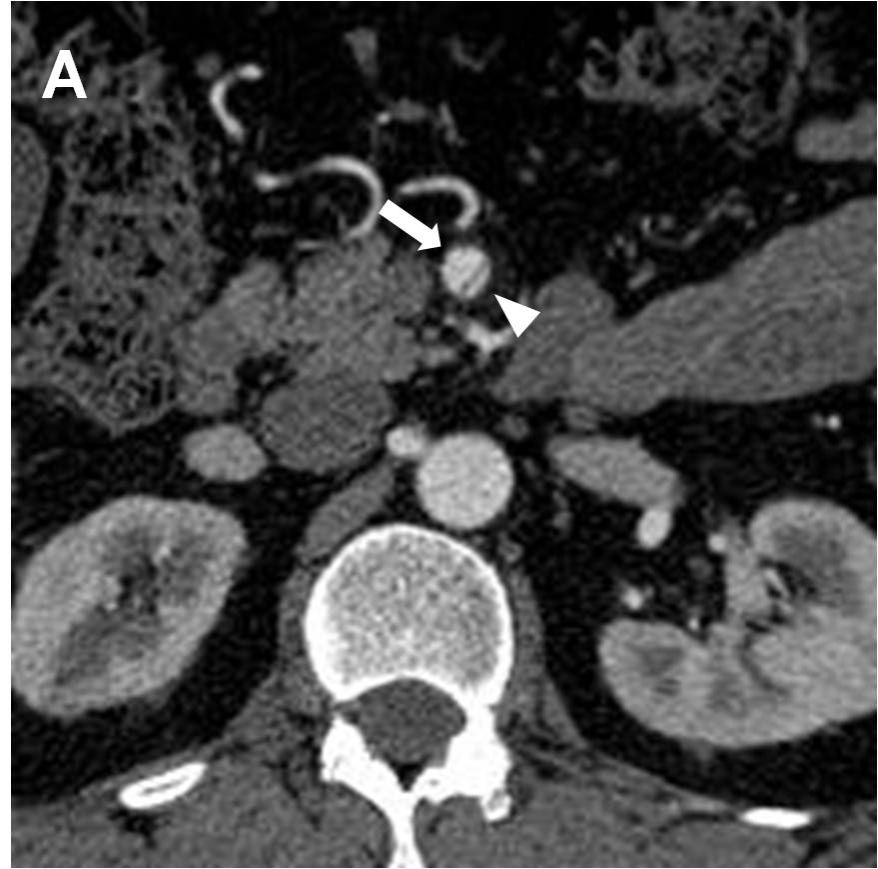

图示:肠系膜上动脉夹层(箭头所示)